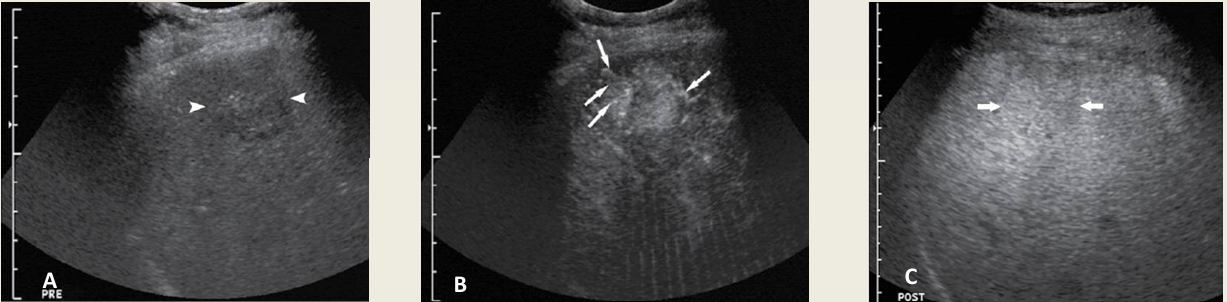

what lesion is this on CEU?

FNH